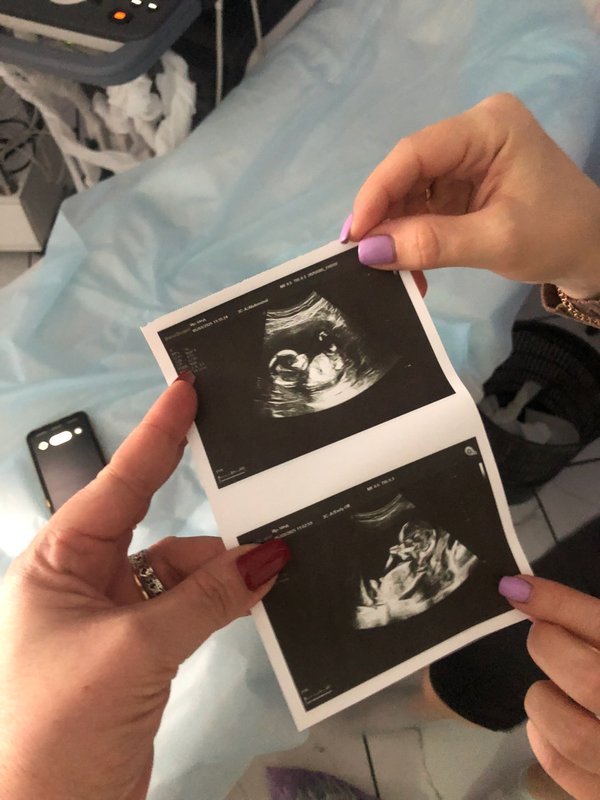

Кажется, еще вчера тест показал две полоски, а сегодня мы уже рассматривали ручки и ножки на мониторе ВАШЕ крошечное солнышко‼️ PS.. группа поддержки в виде ️бабушки и мужа на осмотре . были --- Бородулина Наталья (Врач УЗИ, Косметология) (08.01.2026): Давайте поиграем‼️ Угадайте по фото #УЗИ, кто тут ( Шутка, конечно, рано еще Но верить в чудеса можно уже сейчас). Поделитесь в комментариях своими первыми #фото «горошков», «фасолинок» и «эмбриончиков» устроим галерею самого начала жизни ️

PS.. группа поддержки в виде ️бабушки и мужа на осмотре . были

Бородулина Наталья (Врач УЗИ, Косметология) (08.01.2026):

Угадайте по фото #УЗИ, кто тут ( Шутка, конечно, рано еще Но верить в чудеса можно уже сейчас).

Поделитесь в комментариях своими первыми

#фото «горошков», «фасолинок» и «эмбриончиков» устроим галерею самого начала жизни ️